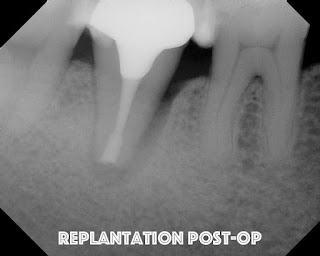

Four years later at another re-evaluation, the bone loss on the lateral is even worse. We are still puzzled at why this has not resolved, but not convinced there is a root fracture, so we decided to try intentional replantation.   So, here are some of the best photos I have to document the process.

The tooth is replanted into the socket within 10 minutes of extraction.  Firm pressure is placed for an extended period of time. No splinting

A seven year recall finds tooth #31 asymptomatic and fully functional.  While the mesial bone looks irregular, there is no periodontal pocket.  If you look at the initial photo of the extracted tooth, you can see the periodontal ligament, but there appears to be an area where the ligament had been lost.  There was not visible fracture on that area of the root at that time.  My assumption is that the pdl may not have ever reformed in that area - causing the current radiographic appearance. It is interesting how a perfectly good root canal and retreatment failed to give the desired results, but a last ditch effort with replantation has been successful up to this point.